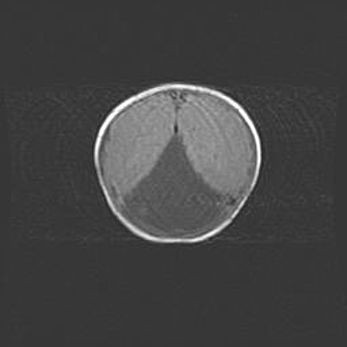

Лейкомаляция с кистозно-глиозной дегенерацией головного мозга.

Возраст: 2 месяца 25 дней

Вес: 6400 г

Окружность головы: 40 см

Срок гестации: 41 неделя

Лейкомаляцию относят к ишемически-гипоксическим повреждениям головного мозга, диагностируемым у новорожденных. При лейкомаляции в головном мозге обнаруживают очаги некроза, возникшие после тяжелой гипоксии и нарушения кровотока. В процессе морфогенеза очаги проходят три стадии: 1) развития некроза, 2) резорбции и 3) формирования глиозного рубца или кисты. Перивентрикулярная лейкомаляция (ПЛ) встречается примерно в 12% случаев среди новорожденных, обычно – у недоношенных детей, причем, частота ее зависит от массы, с которой младенец появился на свет. Наибольшее число малышей страдает лейкомаляцией, если масса при рождении 1500-2500 г.